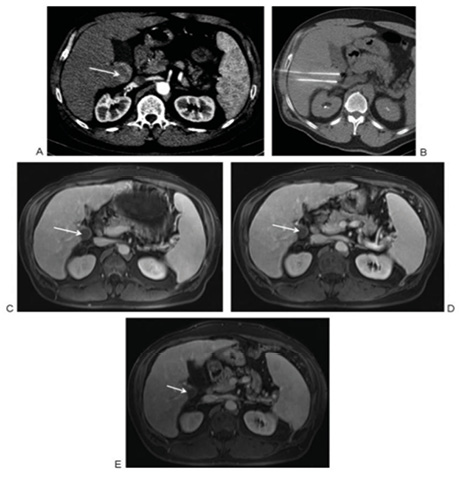

У дослідженні, опублікованому авторами з Маямі, Флорида [6], проаналізовано еволюцію НОЕ, а також її безпеку та ефективність у контексті інших абляційних методів лікування злоякісних новоутворень печінки. Згідно з описом цього дослідження, зазвичай доставляється 90 високовольт­них (1500–3000 В) імпульсів постійного струму (25–45 А) між парою монополярних або одним біполярним електродом (зі зміною лікувальних настанов кількість імпульсів для успішного лікування між парою монополярних електродів була зменшена з 90 до 70). Напруга встановлюється залежно від відстані між кожною парою електродів, з метою генерувати принаймні 1000 В між електродами. Генератор запрограмований на зупинку подачі енергії та перезарядку, якщо сила струму перевищує 48 А. Електроди розміщуються перкутанно під контролем візуалізації (КТ або ультразвукового дослідження) з максимальною відстанню між електродами 2,2 см (рис. 7).

Рис. 7. Процедура НОЕ у пацієнта з біопсійно підтвердженою гепатоцелюлярною карциномою: a) — контрастно підсилене аксіальне КТ-сканування, що проявляє ураження каудальної частки печінки до процедури НОЕ (стрілка); b) — аксіальне КТ-сканування під час процедури НОЕ, що візуалізує 2 монополярні електроди в ураженій частці печінки; c–e) — магнітно-резонансне сканування через 6, 11 та 14 міс після процедури НОЕ, що свідчить про відсутність залишкової або рецидивної пухлини (стрілка) [цит. за 6]